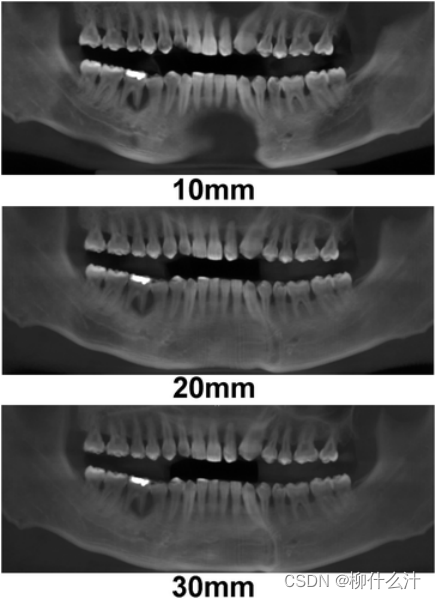

改造可以沿着手动或自动绘制的曲线进行。最常见的是沿牙弓绘制全景曲线,以生成一系列牙齿和骨骼的合成全景图(图00和01)。由于这些合成全景图像的厚度较小,通常不可能在一张图像中看到上下牙弓的情况。因此,通常需要为上、下牙弓分别绘制曲线(图02)。另外,可以计算出这些合成全景图的射线和,类似于从全景X光片上获得的图像。图23显示了不同厚度的合成全景堆叠的射线和全景图像。

不同厚度下的合成射线总和图像。